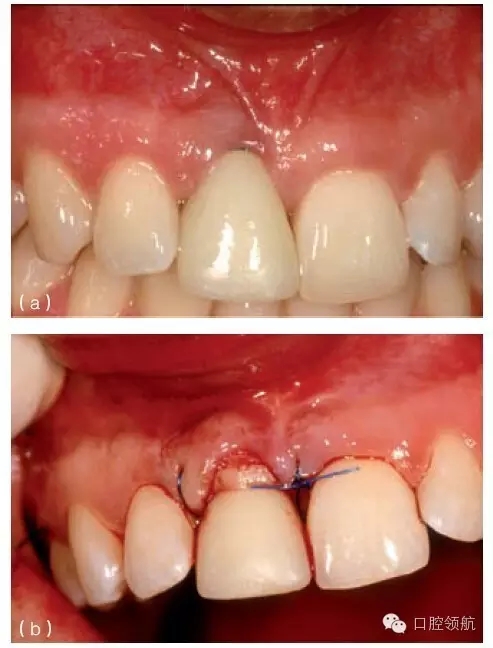

有兩種軟組織移植方法來(lái)恢復(fù)唇側(cè)邊緣退縮的黏膜。第一種方法是,取結(jié)締組織移植到帶有牙冠的種植體的唇面(圖8.22a~c),就類似于根面覆蓋移植術(shù)。翻開(kāi)半厚瓣后,來(lái)源于腭側(cè)的結(jié)締組織移植瓣應(yīng)用懸吊縫合固定到種植體和基臺(tái)的頸部。唇側(cè)瓣冠向復(fù)位覆蓋移植物,并縫合固定在位。這種方法的優(yōu)點(diǎn)如下:

圖8.22 (a)右上頜中切牙(8號(hào)位點(diǎn))種植體和冠初診時(shí)情況。已經(jīng)有黏膜退縮,種植體肩臺(tái)的金屬領(lǐng)圈暴露。(b)治療前,拆下永久冠,粘結(jié)頸部輪廓更為平坦的臨時(shí)冠。做半厚瓣翻瓣,結(jié)締組織移植至?xí)簳r(shí)冠頸部區(qū)域。(c)2個(gè)月愈合期后,黏膜有明顯增厚,但只有約50%的垂直高度得到恢復(fù)。

這種方法的缺點(diǎn)是獲得黏膜覆蓋的可預(yù)測(cè)性有限。最近一個(gè)前瞻性系列病例研究中,10名有單個(gè)種植體位點(diǎn)黏膜退縮的患者接受了聯(lián)合結(jié)締組織移植和冠向復(fù)位瓣,種植體冠保留原位,6個(gè)月后,沒(méi)有位點(diǎn)是完全由移植的軟組織覆蓋,10個(gè)治療的位點(diǎn)平均有66%的覆蓋率。該技術(shù)的不可預(yù)測(cè)性可能是由于如下原因: